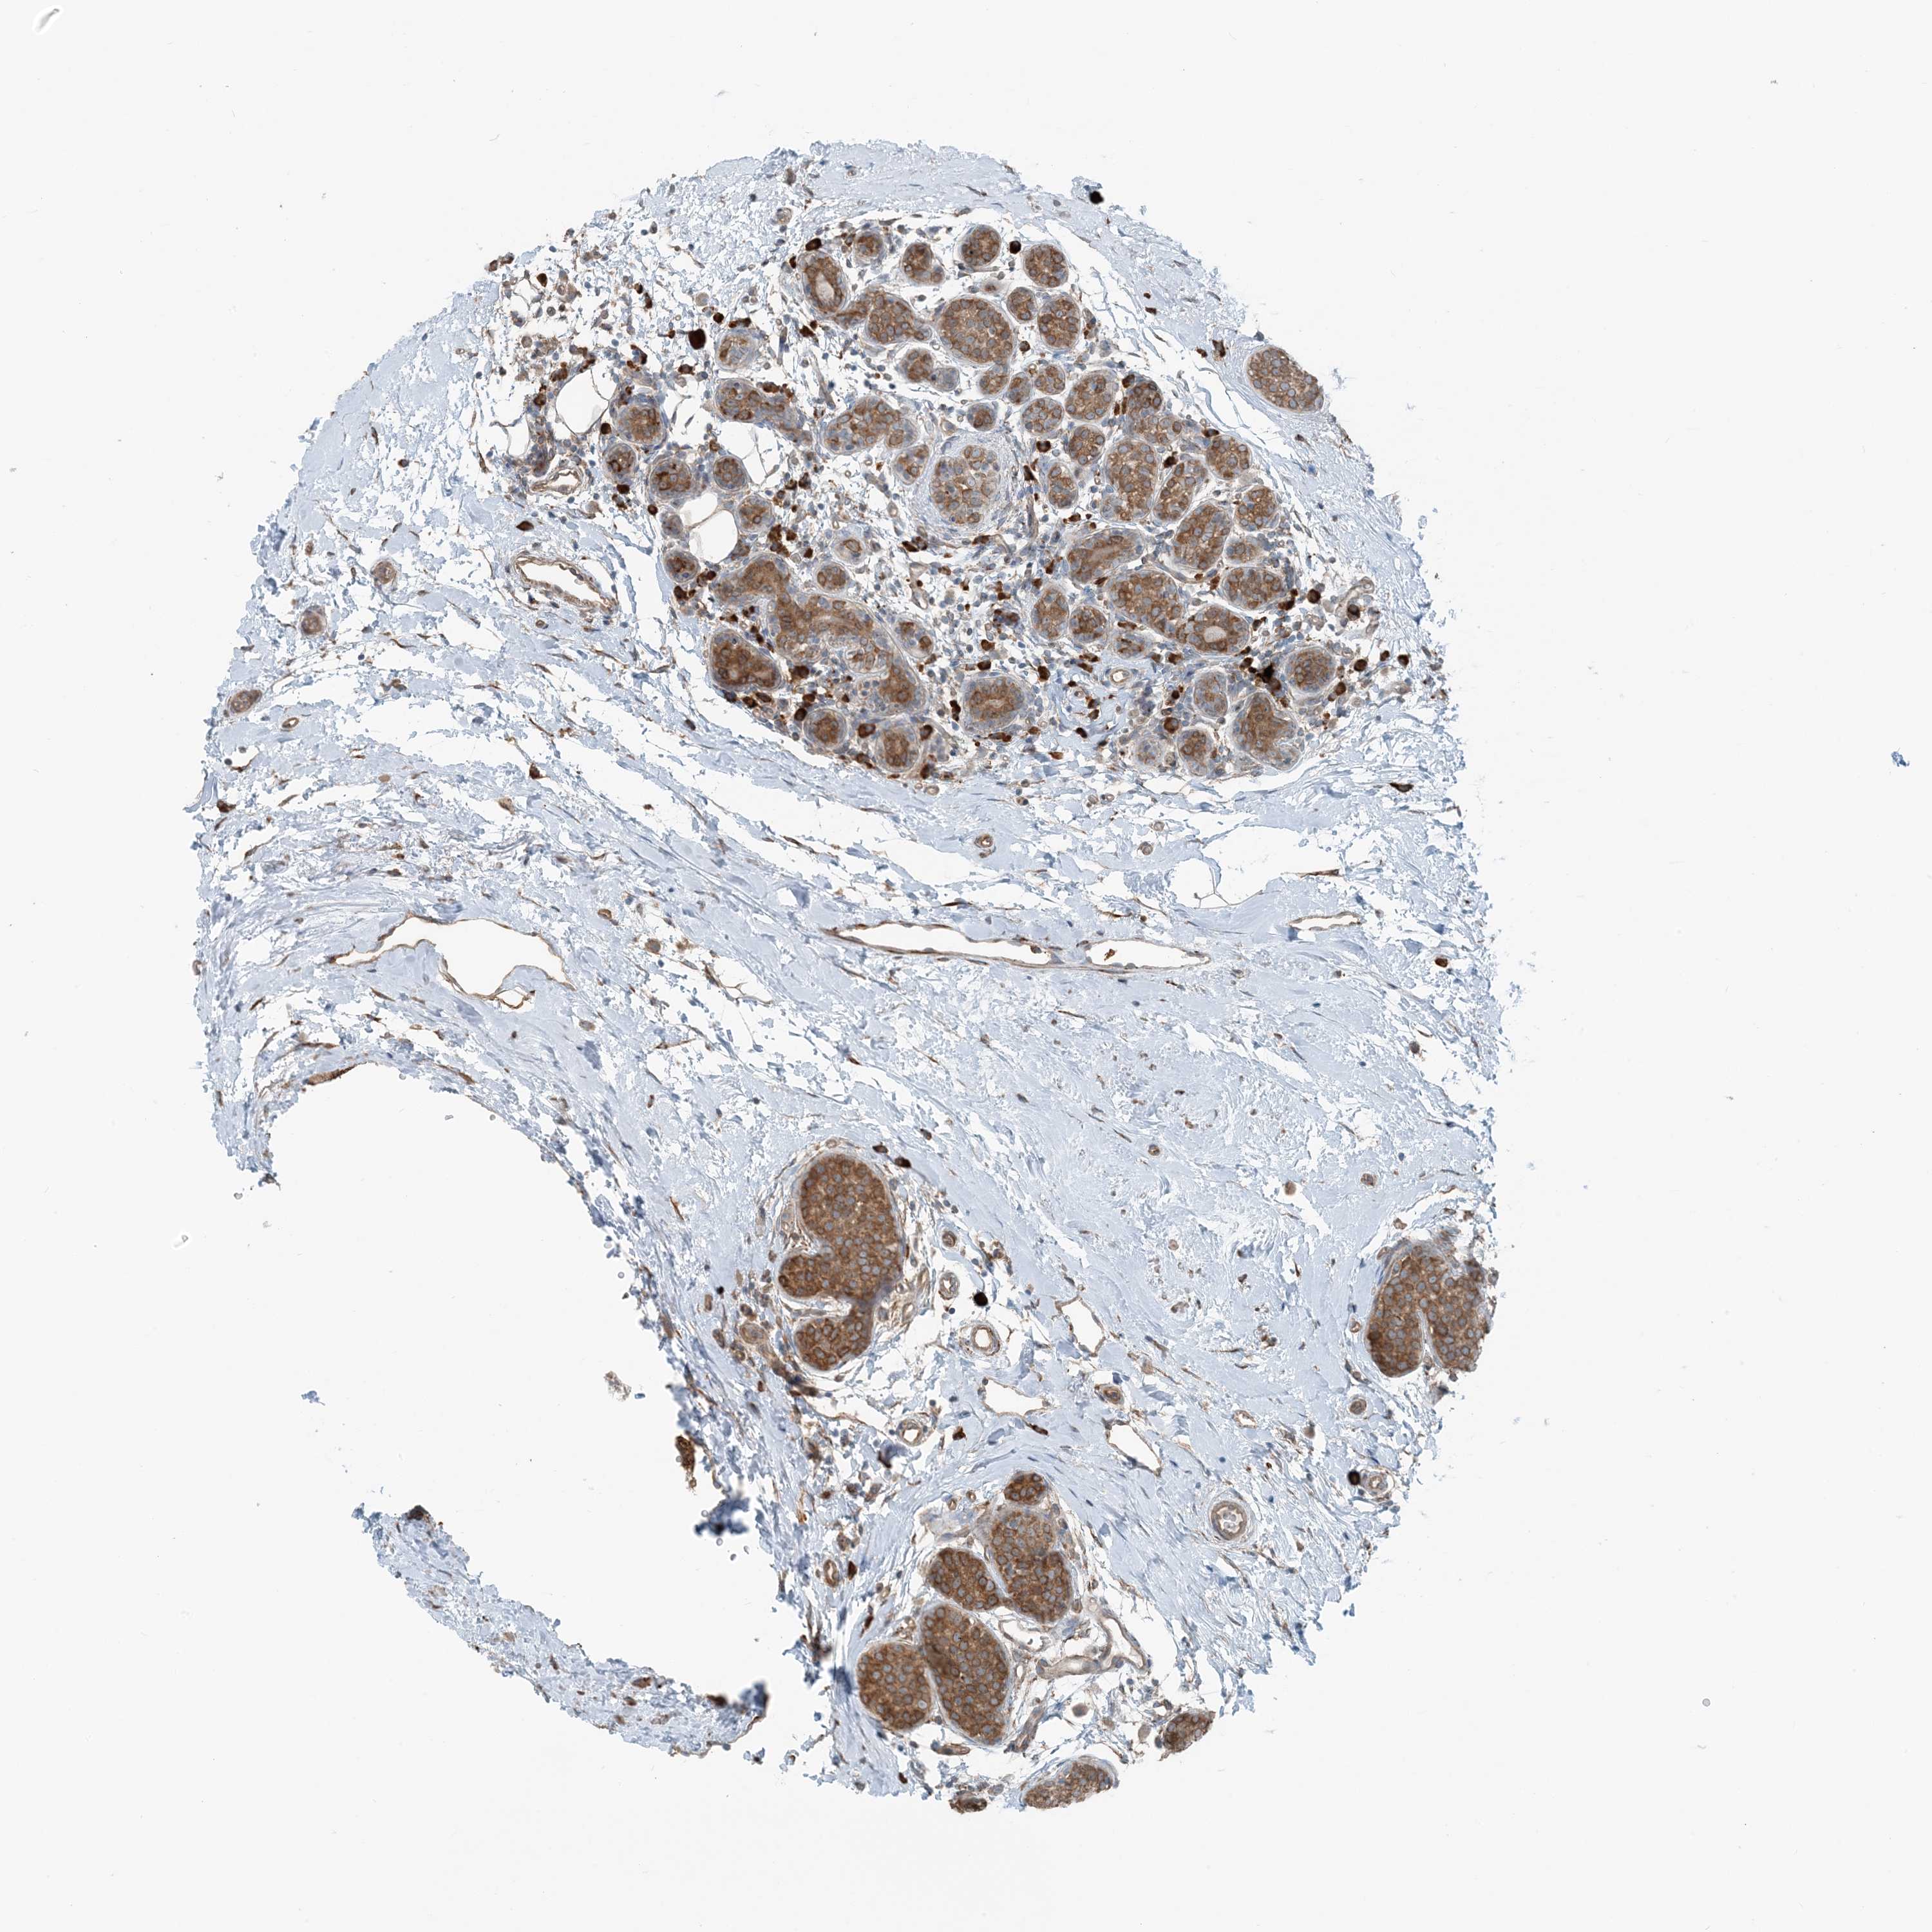

CANCER BREAST CANCER Show tissue menu

BRCA TCGA BRCA VALIDATION PROTEIN EXPRESSION